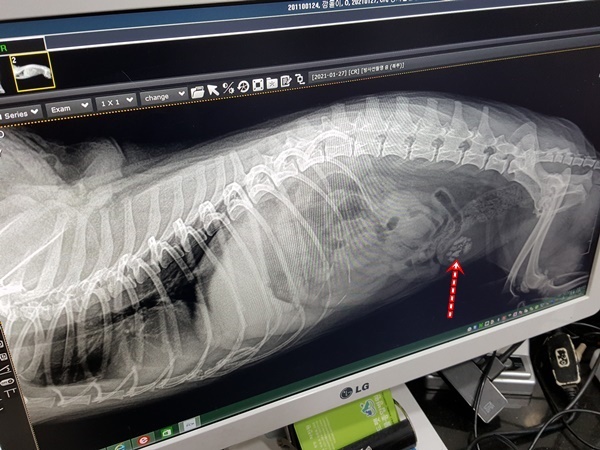

수술전 엑스레이상에..결석이 아래쪽에 뭉쳐있더군요

하나라도 요관으로 빠져나가면 오줌 못누고 막혀서 혈뇨에 응급상황이 오는데..

아직 한번도 그런일이 없었다는게 다행이라고..

깜돌이 방광 요로에 있던 결석입니다